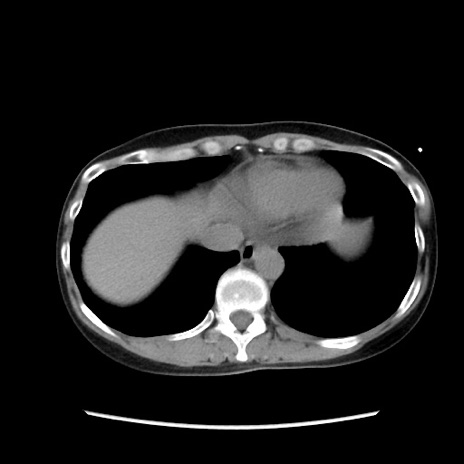

冠状断像

【症例】40歳代 女性

【主訴】上腹部痛、嘔気・嘔吐

【現病歴】約9時間前頃から急に上腹部痛、嘔気、嘔吐が出現。改善しないため救急要請。

【既往歴】子宮頚癌(広汎子宮全摘術、放射線療法)、腸閉塞

【身体所見】腹部:平坦、軟、腸雑音亢進、上腹部を中心に腹部全体に圧痛あり。

【データ】WBC 8400、CRP 0.03